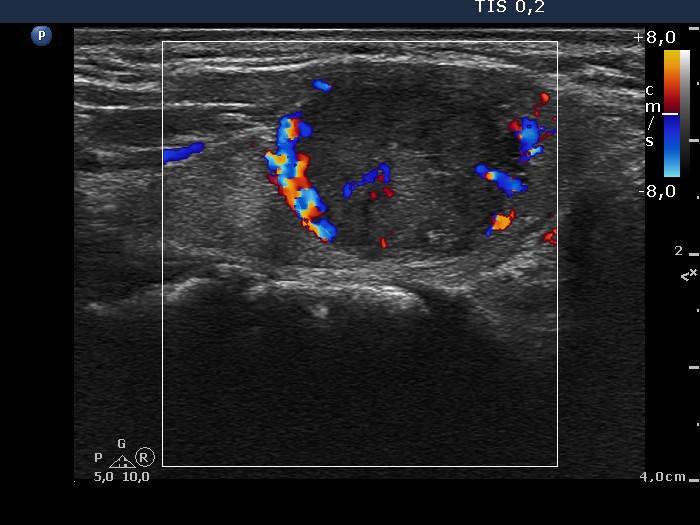

Consecutively operated patients with autoimmune thyroid disease - case 36 (conp 061) (ultrasonographic picture 6)

Right lobe, longitudinal scan, color Doppler mode. The lesion has perinodular and increased intranodular blood flow.